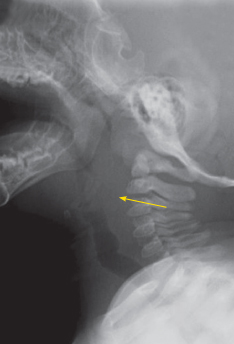

Anteroposterior and lateral views of the soft tissues of the neck are shown.

The anteroposterior radiograph shows an asymmetric soft tissue swelling of the right lateral neck and mild tracheal buckling, which does not indicate mass effect. The lateral view shows widening of the retropharyngeal soft tissues; there is also prominence of the adenoids, with narrowing of the nasopharyngeal airway. Vertebral body alignment and epiglottis, aryepiglottic folds, and glottis appear normal. No foreign body is visible.

The initial step in the evaluation of an infant or child with a potential deep neck space infection is assessment of the airway for obstruction. When the diagnosis is unclear, plain radiographs may be necessary. In patients with a retropharyngeal abscess, the prevertebral space is wider than twice the anteroposterior measurement of the vertebral body: greater than 7 mm at C2 or greater than 14 mm at C6. The soft tissue inflammation (phlegmon or abscess) may also reverse the normal lordotic cervical spine curvature. When suspi- cion is high, a CT scan with intravenous contrast is the preferred study to assess abscess formation and extent of disease.1